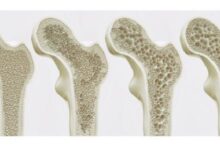

- الكورتيكوستيرويد (بالإنجليزية: Corticosteroids): يتمّ استخدامها للمرضى الذين لا يمكنهم استخدام مضادات الالتهاب غير الستيرويديّة أو الكولشيسين، ويمكن إعطاء هذه الأدوية عن طريق الفم أو عن طريق حقنها داخل الوريد أو حقنها في العضلات أو حقنها داخل المفصل، حيث تُستخدم الأخيرة في الحالات التي تحدث فيها النوبات في مفصلٍ واحدٍ، وذلك عن طريق إعطاء حقنةٍ طويلة المفعول بهدف تقليل التأثيرات على كامل أجهزة الجسم عند أخذ الكورتيكوستيرويد الفموي، ولكن يجب التأكد من عدم وجود التهابٍ قبل إعطائها. ومن المهمّ اتخاذ الإجراءات لمنع حدوث هشاشة العظام في حالات العلاج بالكورتيكوستيرويد التي تمتدّ لأكثر من أسبوعين.